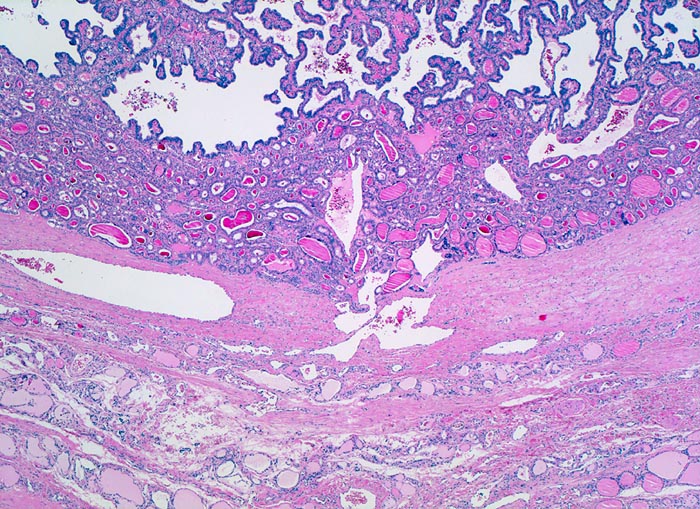

Histologisch finden sich bei der klassischen Variante des papillären Schilddrüsenkarzinoms verzweigte Papillen mit einem zentralen fibrovaskulären Stiel und/oder Follikel, welche von Zellen mit den morphologischen Charakteristika eines papillären Karzinoms ausgekleidet sind. In der Hälfte der Fälle können Verkalkungen in Form von Psammomkörperchen nachgewiesen werden. Bei der follikulären Variante des papillären Karzinoms bilden die Tumorzellen Follikel. Die neoplastischen Follikel sind von Zellen mit der typischen Morphologie des papillären Karzinoms (gekerbte Kerne mit aufgelockertem Chromatin und intranukleäre Vakuolen (> 5425)) ausgekleidet. Daneben existieren verschiedene weitere histologische Subtypen des papillären Karzinoms: kolumnarzellige Variante (columnar cell), großzellige Variante (tall cell), diffuse sklerosierende Variante, onkozytäre Variante, und solide Variante. Kombinationen dieser Subtypen kommen vor. Die diffuse sklerosierende Variante (2% der Fälle), welche bei jüngeren Patienten auftritt, kann eine Struma ohne palpable Knoten ausbilden und klinisch mit einer Autoimmunthyreoiditis verwechselt werden.

• Scharf begrenzter Tumor mit schmaler Kapsel.

• Links im Bild sind Reste von nicht neoplastischem Schilddrüsenparenchym sichtbar.

• Der Tumor besteht aus Papillen mit einem fibrovaskulären Stromastiel und neoplastischen Follikeln.